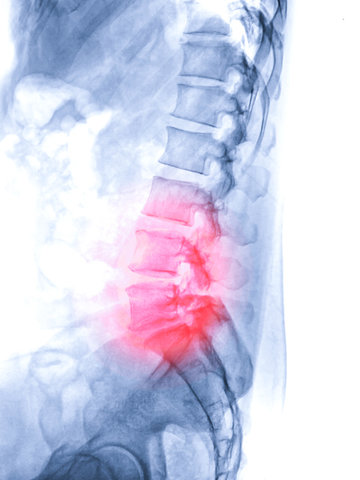

Nyeri punggung bawah merupakan salah satu keluhan yang paling sering dialami masyarakat. Pada sebagian orang, nyeri ini bisa terasa ringan dan hilang dengan istirahat. Namun, pada kondisi tertentu, nyeri punggung bawah bisa menetap, menjalar ke kaki, hingga mengganggu aktivitas sehari-hari. Salah satu penyebab yang sering terjadi adalah saraf kejepit pada tulang belakang.

Saraf kejepit terjadi ketika saraf tulang belakang tertekan oleh jaringan di sekitarnya, seperti bantalan tulang, tulang, atau ligamen. Kondisi ini sering terjadi di area punggung bawah dan dapat disebabkan oleh: